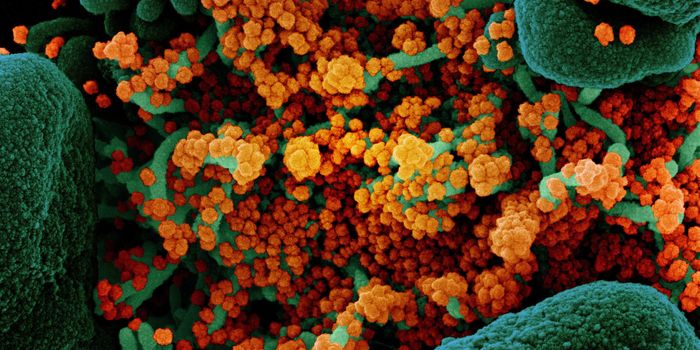

MAR 14, 2022ImmunologyThough it may happen at different rates for different microbes, mutations happen, and SARS-CoV-2, the virus that causes ...